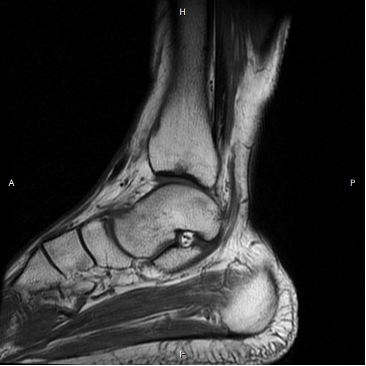

患者详情: 6月前无明显诱因右脚酸痛。踝部平扫CT(体检):右侧距骨前部骨质破坏,考虑肿瘤性病变,良性可能。右侧距骨滑车及胫骨下段关节面下局部骨质破坏。踝部平扫MRI(体检):右侧距骨前部大片异常信号伴骨皮质破坏,肿瘤病变可能大,胫骨远端关节面下小片异常信号,胫骨下段和跟骨上缘下少许骨髓水肿可能。右踝关节积液。PET-CT(上海交大附属新华医院):右侧股骨、胫骨、腓骨、右侧距骨、右第5足趾多发低密度骨质破坏伴代谢异常增高,恶性病变可能,LCH不除外,建议活检明确。上海交大附属新华医院全麻下行右距骨骨肿瘤切除+活检+距舟关节植骨融合术+石膏外固定。

影像学检查:(点击查看大图)